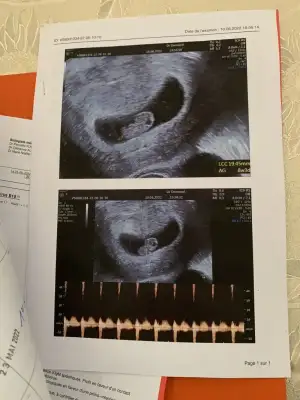

5 ve 14. haftaya kadar olan ultrason fotolarınızı paylaşın. Vajinadan mı yoksa karından mı çekildiğini ve kaç haftalık olduğunu da mutlaka belirtin.:anneadayı:

Merhaba 13+3 karından çekılmıs ultrason. Tahmınınız nedir rica etsem?